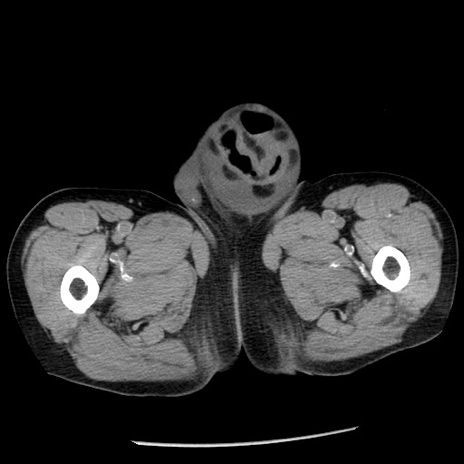

症例26(横断像)

【症例】80歳代男性

【主訴】嘔吐

【現病歴】昨晩2回嘔吐あり、今朝になっても嘔吐あり。来院。

【既往歴】胃潰瘍

【身体所見】意識清明、BT 37.6℃、BP 166/95mmHg、HR 100bpm、SpO2 97%、腹部:平坦・軟、腸蠕動音聴取良好、圧痛なし。

【データ】WBC 21900、CRP 1.46